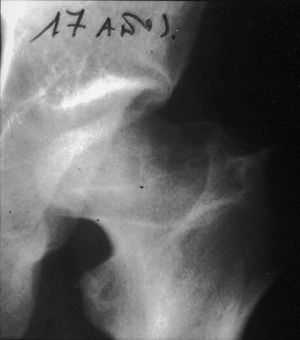

A continuación se describe el caso de un varón de 4 años y 5 meses de edad con dolor en rodilla izquierda de 4 meses de evolución, sin síntomas de infección. En la exploración física se observó una limitación comparativa de la rotación interna de la cadera izquierda, sin ninguna otra limitación en esa extremidad. Las radiografías mostraron alteración epifisaria proximal femoral compatible con necrosis de la cadera izquierda (fig. 1). El niño no presentaba ningún signo que hiciera sospechar displasia ósea. Con estos hallazgos clínicos y radiológicos se diagnosticó enfermedad de Legg-Calve-Perthes. Se administró tratamiento conservador mediante antiinflamatorios no esteroideos y férula de abducción de Thomas durante 3 años y se realizó seguimiento con controles clínicos y radiológicos. Después de 3 años el niño se encontraba asintomático y las pruebas de imagen mostraban una evolución favorable: se apreciaba remodelación completa de la cabeza femoral y morfología clase I según la clasificación de Stulberg1. El niño fue dado de alta, lo que le permitió vida normal.